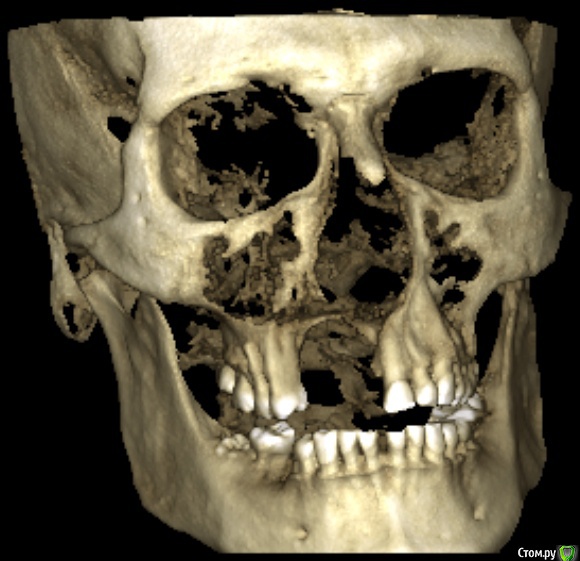

L.E.S.I.K. Опубликовано 13 июля, 2017 Поделиться Опубликовано 13 июля, 2017 Доброго времени суток, коллеги. Пациент обратился с желанием иметь несъемную конструкцию на имплантах. В анамнезе 5 мес назад операция по поводу хронического одонтогенного остеомиелита верхней челюсти. В настоящее время клинический признаков воспаления нет. Есть только значительный дефект. 3 класса по Зиберту. Какие возможны методы аугментации кости в объеме необходимом для имплантации? Мне на ум приходит только блоки из подвздошной Ссылка на комментарий

Bier Опубликовано 13 июля, 2017 Поделиться Опубликовано 13 июля, 2017 плохие очень снимки, толком ничего не понятно. Блоки с подвздошки забудьте, они резорбируются быстро. Тут нужен один из вариантов GBR Покажите нормальные срезы, чтобы был ясен уровень костных пиков на соседних зубах. Ссылка на комментарий

L.E.S.I.K. Опубликовано 13 июля, 2017 Автор Поделиться Опубликовано 13 июля, 2017 Возле 21 пик есть, а в обл 25 снижен, корень оголен на четверть. Смущает также отсутствие местами костно дна полости носа Ссылка на комментарий